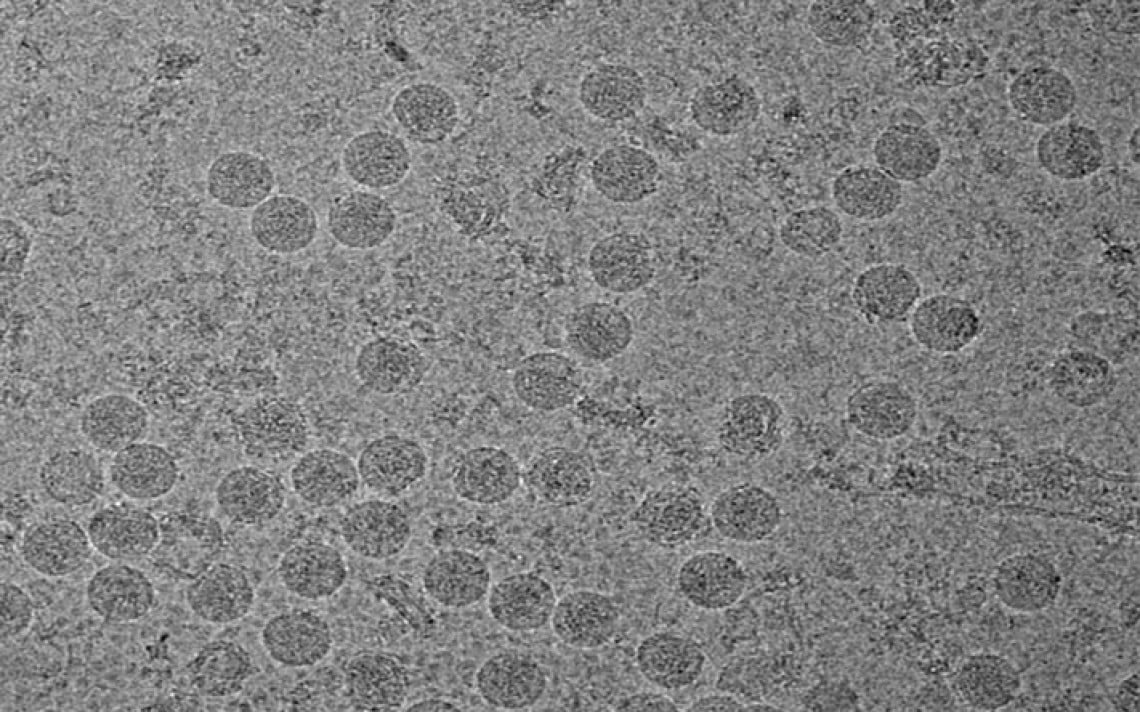

O vírus da zika pode se reproduzir na vagina durante vários dias após a infecção, afirmaram na quinta-feira (25) pesquisadores americanos que estudaram a transmissão sexual do vírus em roedores.

A reprodução do zika através do trato vaginal pode ser uma fonte potente de infecção "com consequências potencialmente desastrosas", ressaltou o estudo realizado pela Universidade de Yale e publicado na revista científica "Cell".

Fêmeas de camundongo grávidas foram infectadas por via vaginal com o zika, que se espalhou dos genitais para o cérebro do feto.

"Vimos uma replicação significativa do vírus no tecido genital, em quatro a cinco dias", disse Akiko Iwasaki, professora de Imunobiologia e pesquisadora do Howard Hughes Medical Institute.